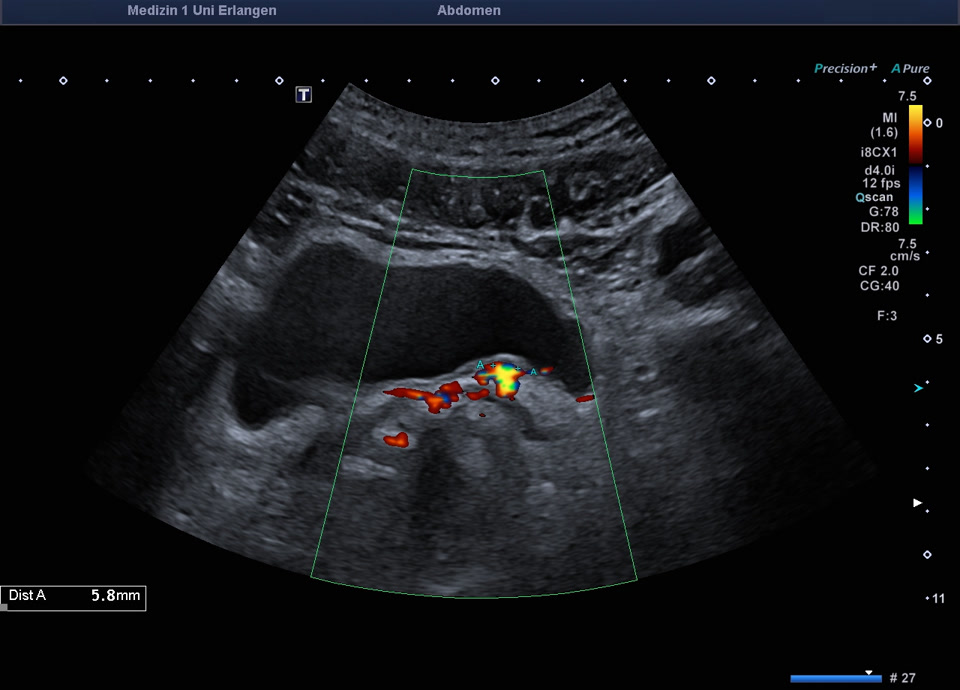

55-jähriger Patient mit abdominellen Beschwerden. Sonographisch stellt sich die linke Niere mit einem altersentsprechenden Parenchymsaum und regelrechter Mark-/Rindendifferenzierung dar. Das Nierenbeckenkelchsystem ist nicht erweitert. Distal im Bereich des Harnblasenostiums zeigt sich ein Konkrement von ca. 6 mm im Ureter, begleitet von positivem Twinkling-Artefakt im Farbdoppler. Der Ureter ist diskret erweitert, proximal bis 10mm. Sonographischer Befund vereinbar mit einer Ureterolithiasis im distalen linken Ureter (Ostium Harnblasenboden).